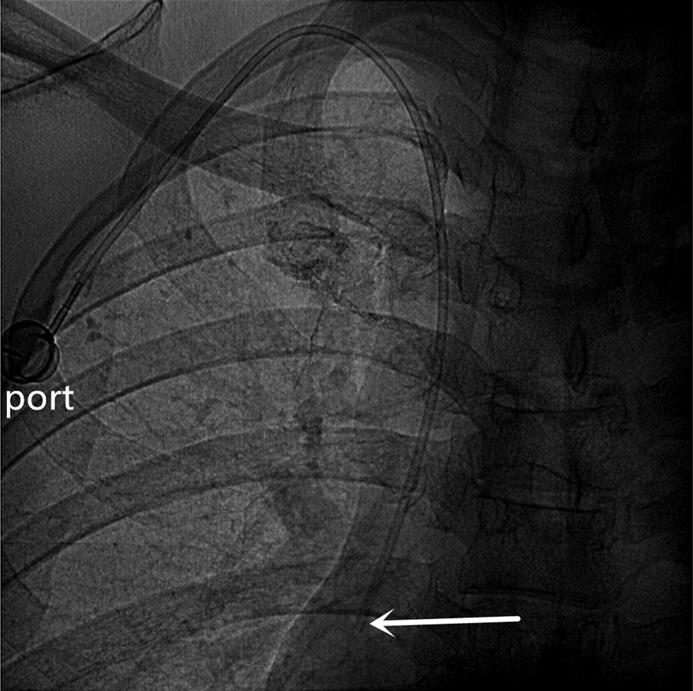

An artificial pocket of the appropriate size was created on the upper part of the chest wall, just enough to contain the port. A tunnel needle crossed over the supraclavicular region to connect the catheter and port in the pocket, and its tip was adjusted to the junction of the superior vena cava and the right atrium under fluoroscopy (Figures 3 and 4). Blood infusion and withdrawal were tested again to ensure that the infusion port functioned normally after the incision was closed.

Figure 4

A totally implantable venous access port (TIVAP) is implanted via the left BCV approach, crossing over the left clavicle. The port is located on the left chest wall, and the tip of the catheter (white arrow) is located at the junction of the superior vena cava and the right atrium.